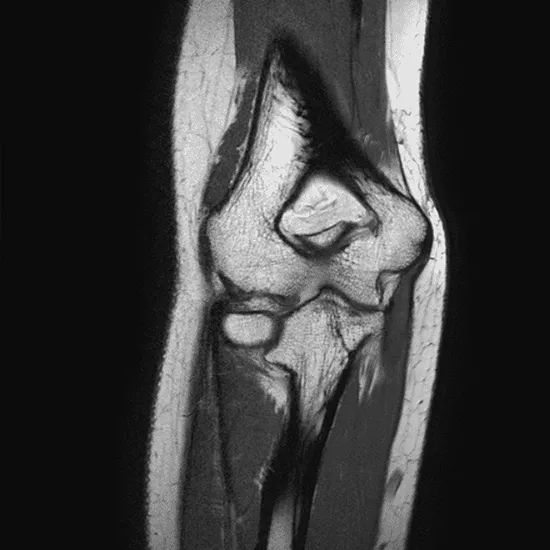

MRI scans of the elbow can reveal detailed images of structures within the elbow joint, including abnormalities with bone, blood vessels, nerves, and soft tissue.

An elbow MRI can help determine the source of discomfort, stiffness, and edema in the joint and the soft tissue surrounding it, such as the tendons and ligaments.